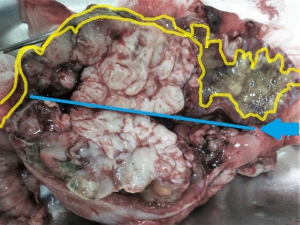

下の写真は手術時のもので、小腸の腫瘤を取り出しているところです。刺激的な写真のため、いつものようにやや色調を落としてありますが、注意してご覧になってください。

この腫瘤はまるでロールキャベツのように周囲に大網(胃の下方へエプロンのように腸の全面に垂れ下がった腹膜のこと)、がかなり癒着しておりました。また、一部、穿孔(穴が開くこと)した跡が見られ、その部分に特に強い癒着があります。(右上やや赤い組織)

下は、腫瘤を裏返したところですがここにも大網、腸間膜との癒着があり、中央部に穿孔した跡らしい癒着が見られます。